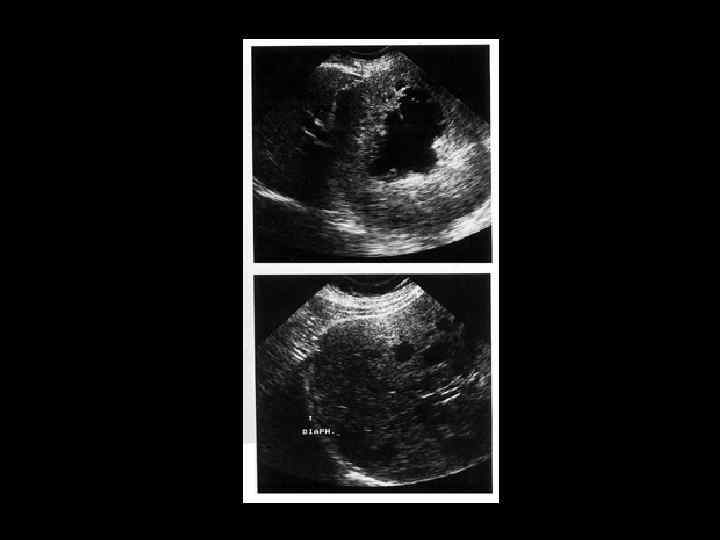

АКТУАЛЬНЫЕ ВОПРОСЫ РЕНТГЕНОЛОГИИ ЛУЧЕВАЯ ДИАГНОСТИКА ОЧАГОВЫХ ПОРАЖЕНИЙ ПЕЧЕНИ АБСЦЕСС ПЕЧЕНИ Ультразвуковая семиотика: - гипоэхогенное образование - округлой формы - неоднородной структуры - прослеживаются внутренние стенки - контуры менее ровные, чем у кисты - вокруг полости - изменения паренхимы

АКТУАЛЬНЫЕ ВОПРОСЫ РЕНТГЕНОЛОГИИ ЛУЧЕВАЯ ДИАГНОСТИКА ОЧАГОВЫХ ПОРАЖЕНИЙ ПЕЧЕНИ АБСЦЕСС ПЕЧЕНИ Компьютерно-томографическая семиотика: - образование низкой плотности (20 -30 ед. Н) - видна капсула с нечетким внутренним контуром - вокруг полости ободок измененной паренхимы - при введении РКВ - усиление изображения стенок

АКТУАЛЬНЫЕ ВОПРОСЫ РЕНТГЕНОЛОГИИ ЛУЧЕВАЯ ДИАГНОСТИКА ОЧАГОВЫХ ПОРАЖЕНИЙ ПЕЧЕНИ АБСЦЕСС ПЕЧЕНИ МР семиотика: - на Т 2 взвешенных изображениях - образования с усиленным сигналом - при контрастном усилении - картина та же, что и при КТ